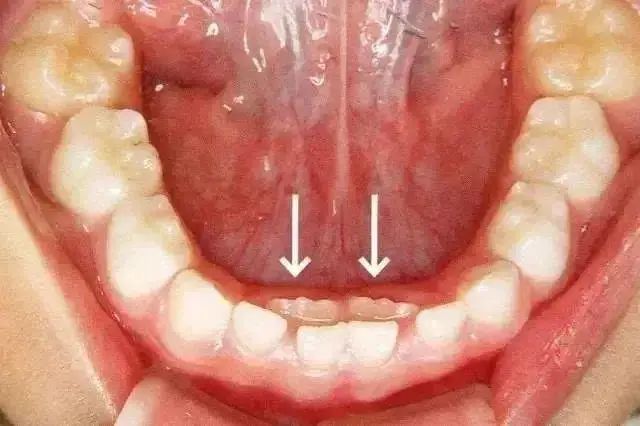

乳牙滞留是指恒牙相继长出,乳牙未能及时脱落。或者恒牙未萌出,保留在恒牙列中。乳牙的脱落与恒牙的生长之间存在着密切的关系。这种情况多见于换牙期的下颌门牙,恒牙长在舌侧,乳牙留于唇侧,出现双排牙。

过早过多的拔牙,容易造成孩子牙颌畸形,拔不拔牙首先要看恒牙萌出的高度,当恒牙只萌出 1/3 或者 2/3 ,且前排牙齿还没有松动的情况下,建议家长先让孩子多吃硬性食物,比如啃苹果、玉米等,促进自然脱落。

恒牙已经完全长出来,保留下来的乳牙应该马上拔掉。将下颌的乳牙拔掉后,长在后面的恒牙可以恢复正常的排列。如果牙齿排列不当,应选择恰当时间矫正!乳牙拔除过程中可能出现根断裂,由于残根较接近恒牙,可以不治疗,牙根会被自身吸收或随着恒牙的爆发脱落。